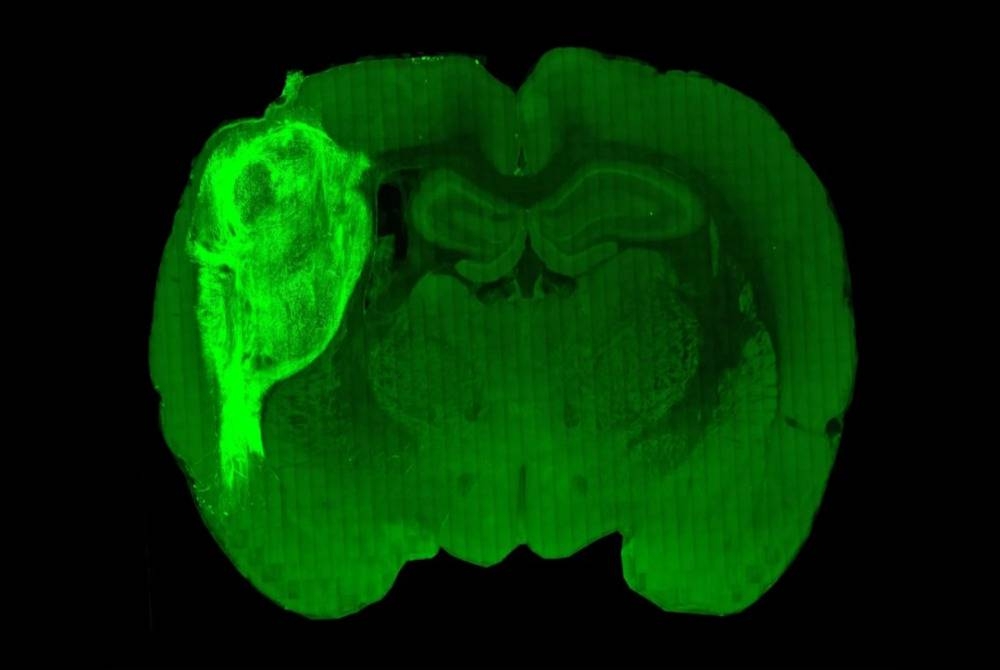

Para penyelidik menanam kumpulan sel otak manusia dipanggil sebagai organoid ke dalam otak tikus muda.

"Dengan memindahkannya pada peringkat awal ini, kami mendapati bahawa organoid ini boleh tumbuh agak besar.

"Ia menjadi vaskular (menerima nutrien) oleh tikus dan boleh meliputi kira-kira satu pertiga daripada otak tikus," kata Sergiu Pasca iaitu pengarang utama kajian dan profesor psikiatri serta sains tingkah laku di Universiti Stanford, California seperti dilaporkan AFP.